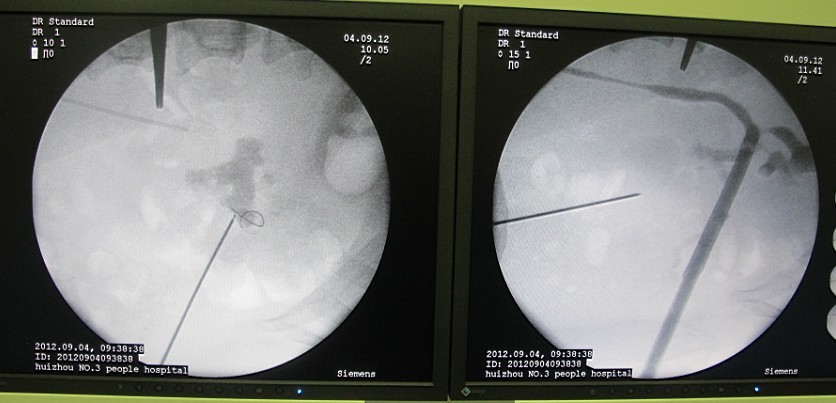

5术前和术后C臂透视可见通道异常精确自中小盏抵达肾盂出口。对比可以清晰的看到结石已完全清除。